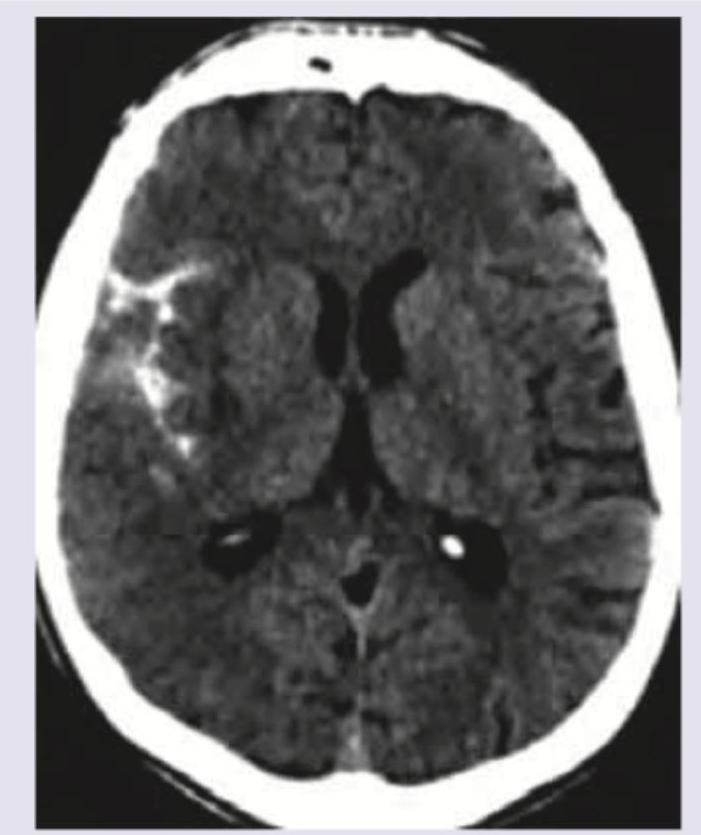

Question 3: A 35-year-old woman presents with thunderclap headache. NCCT was done. All are true about the condition except:

Explanation: The image provided appears to be a **Non-Contrast CT (NCCT) scan of the brain**, showing a **hyperdense area** in the right hemisphere, consistent with **subarachnoid hemorrhage (SAH)** given the context of a "thunderclap headache." Thunderclap headache is a classic symptom of SAH. ***Most common cause of death is rebleeding*** - While rebleeding is a **serious complication** and contributes significantly to morbidity and mortality in SAH patients, the most common cause of death following SAH, particularly in the acute phase, is often related to the **initial hemorrhage** itself, such as **brain herniation**, or **early hydrocephalus** and **vasospasm-induced cerebral ischemia**. - **Vasospasm**, leading to **delayed cerebral ischemia (DCI)**, is a major cause of death and disability in SAH survivors, but the question asks about the "most common cause of death," which in many cases is the immediate devastating effect of the initial bleed or its early complications rather than rebleeding alone. *Hyponatremia* - **Hyponatremia** is a common electrolyte imbalance seen in patients with SAH, often due to **Syndrome of Inappropriate Antidiuretic Hormone (SIADH)** or **Cerebral Salt Wasting (CSW)**. - Therefore, the statement that hyponatremia occurs is **true** for this condition. *Prolonged QT interval* - **Cardiac abnormalities**, including **ECG changes** such as **QT prolongation**, T-wave inversion, and ST depression, are frequently observed after SAH due to **autonomic nervous system dysfunction** and catecholamine release. - Therefore, the presence of a prolonged QT interval is **true** for this condition. *Nimodipine is drug of choice* - **Nimodipine** is a **calcium channel blocker** widely used in SAH patients to **prevent or reduce the severity of cerebral vasospasm** and associated delayed cerebral ischemia. - It is currently the **drug of choice** for this indication in SAH, making this statement **true**.

Question 4: A 50-year-old hypertensive patient develops sudden onset drooping of right face and hemiplegia. What is the diagnosis?

Explanation: ***MCA area hemorrhage*** - The **hyperdense lesion** on CT scan indicates **acute hemorrhage** in the MCA territory, which correlates with the sudden onset right facial droop and hemiplegia. - **Hypertension** is the most common risk factor for primary **intracerebral hemorrhage**, and MCA territory involvement typically causes contralateral face and arm weakness. *MCA area infarction* - **Infarctions** appear as **hypodense (dark) areas** on CT scan, not hyperdense lesions as described in this case. - While MCA infarction can cause similar clinical symptoms, the imaging findings clearly show hemorrhage rather than ischemic changes. *ACA area infarction* - **ACA infarction** typically presents with **leg weakness** more prominent than face/arm weakness, as the ACA supplies the medial motor cortex for lower limbs. - The imaging shows a **hyperdense hemorrhage**, not the **hypodense appearance** characteristic of infarction. *ACA area hemorrhage* - **ACA territory hemorrhage** would affect the **frontal lobe**, causing symptoms like leg weakness, **abulia** (lack of motivation), and urinary incontinence. - The clinical presentation of **facial droop and hemiplegia** involving face and arm is more characteristic of **MCA involvement** rather than ACA territory.